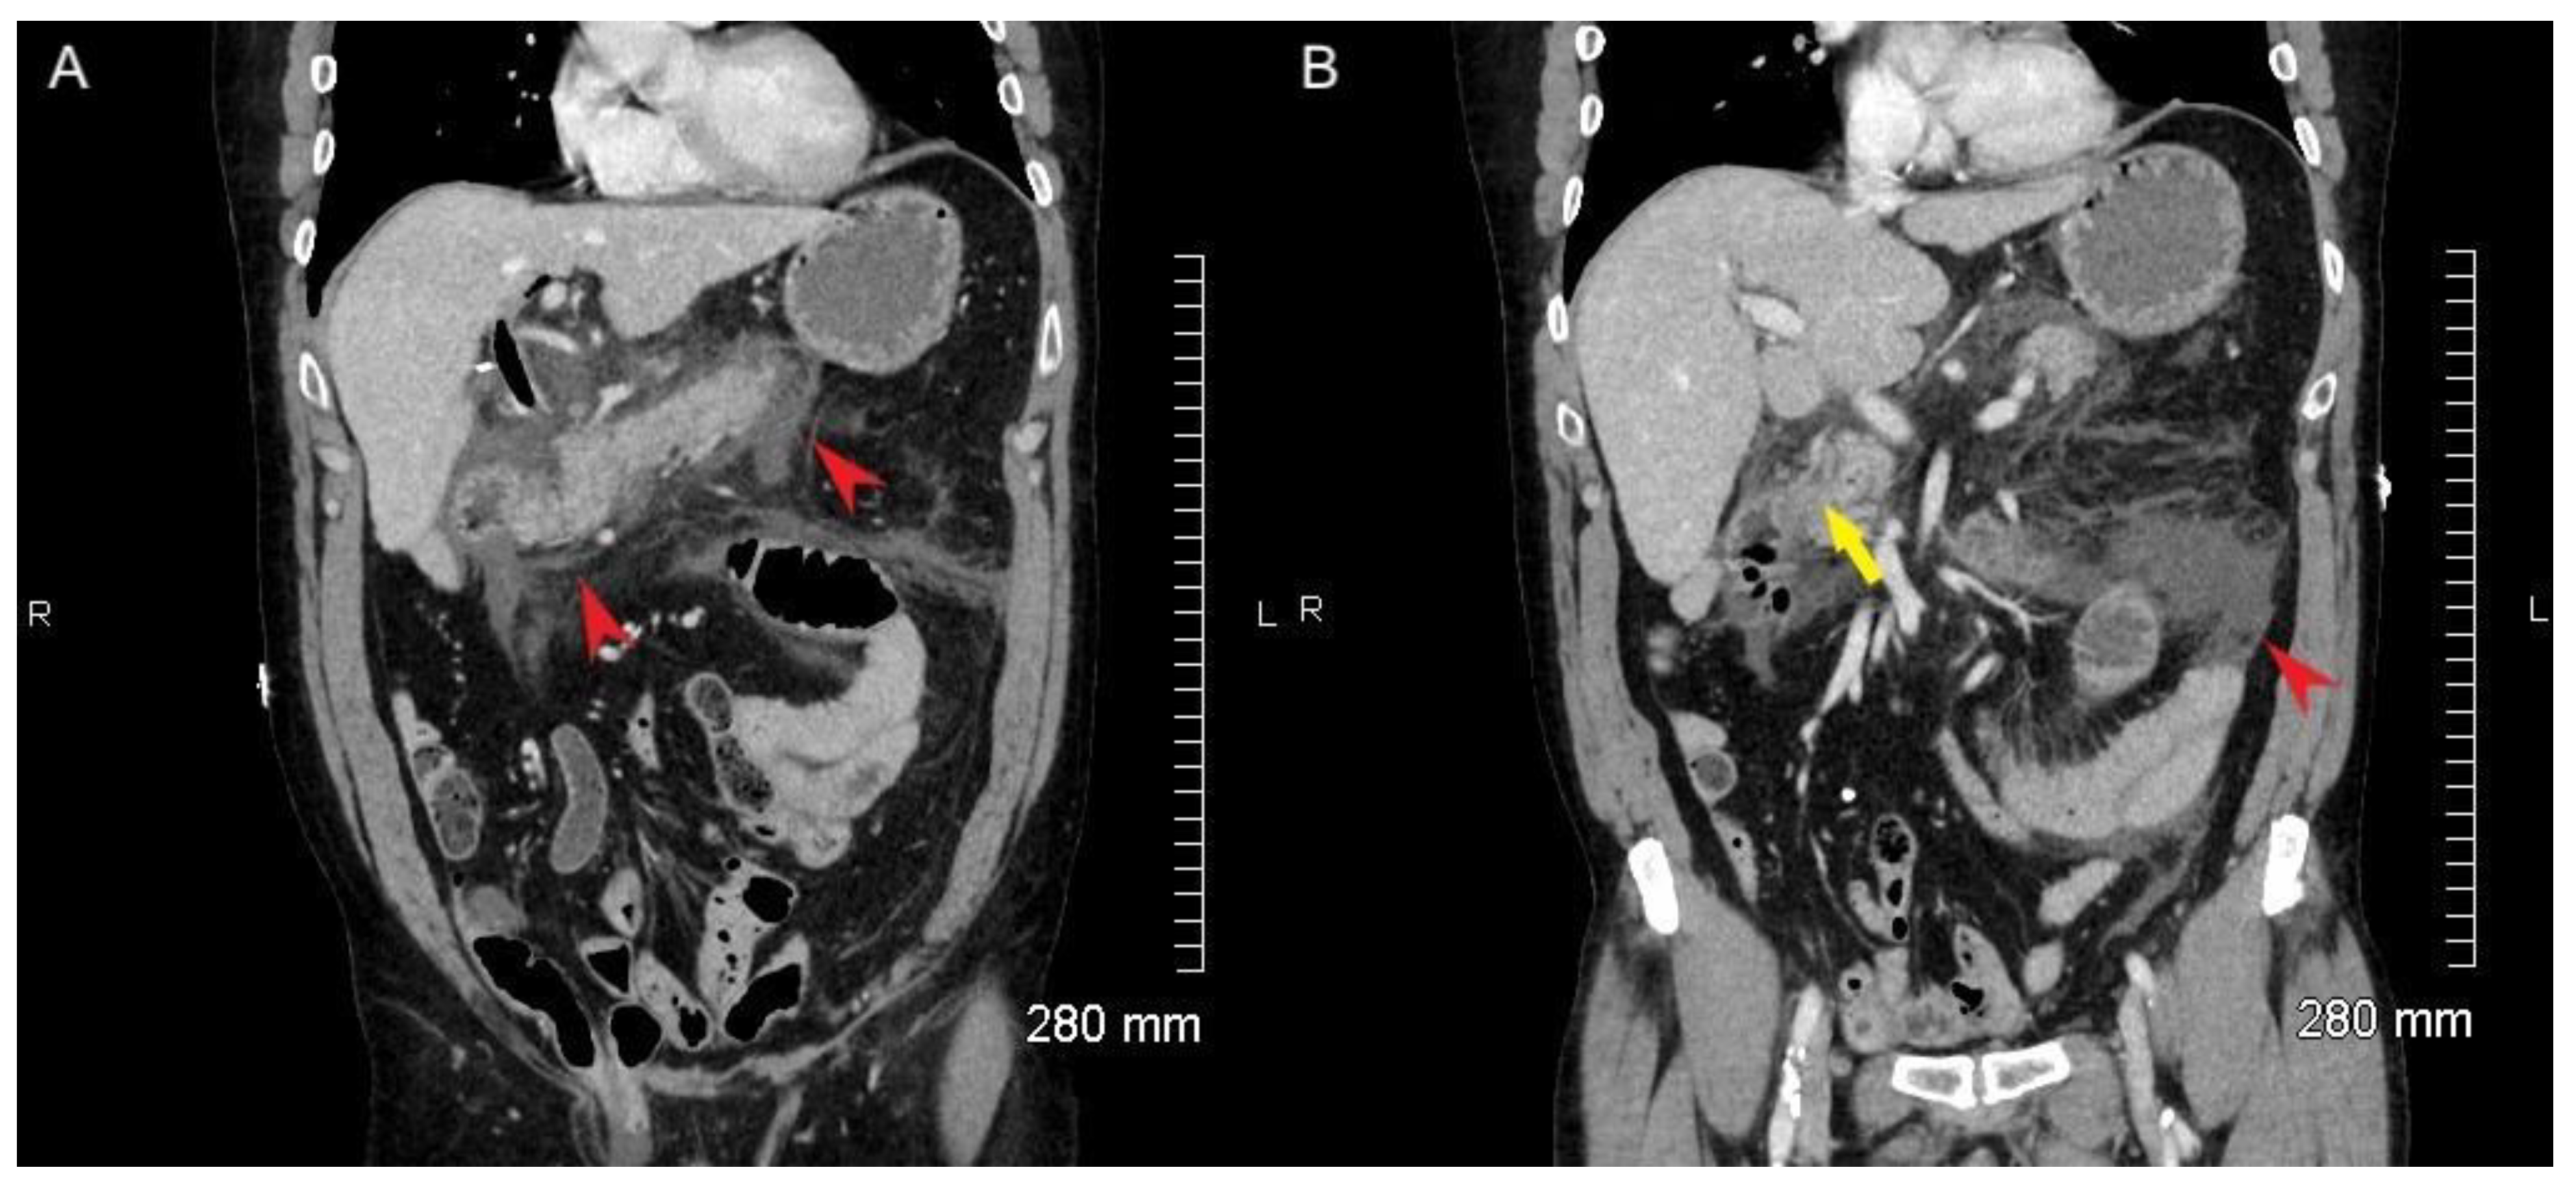

2. Case Report